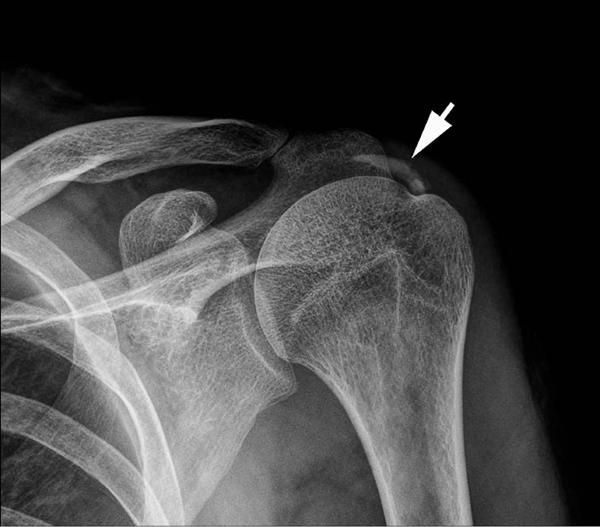

從上述的身體檢查,大致可推斷哪一條或哪幾條肌腱有問題,但要確定是否有鈣化性肌腱炎,需借助於影像檢查,如一般X光(圖1)、超音波(圖2)或磁振造影檢查。

穿刺或抽吸是在超音波的導引下,使用18至22號針頭多次穿刺或抽吸鈣化物,以加速鈣化物的排除(圖4)。